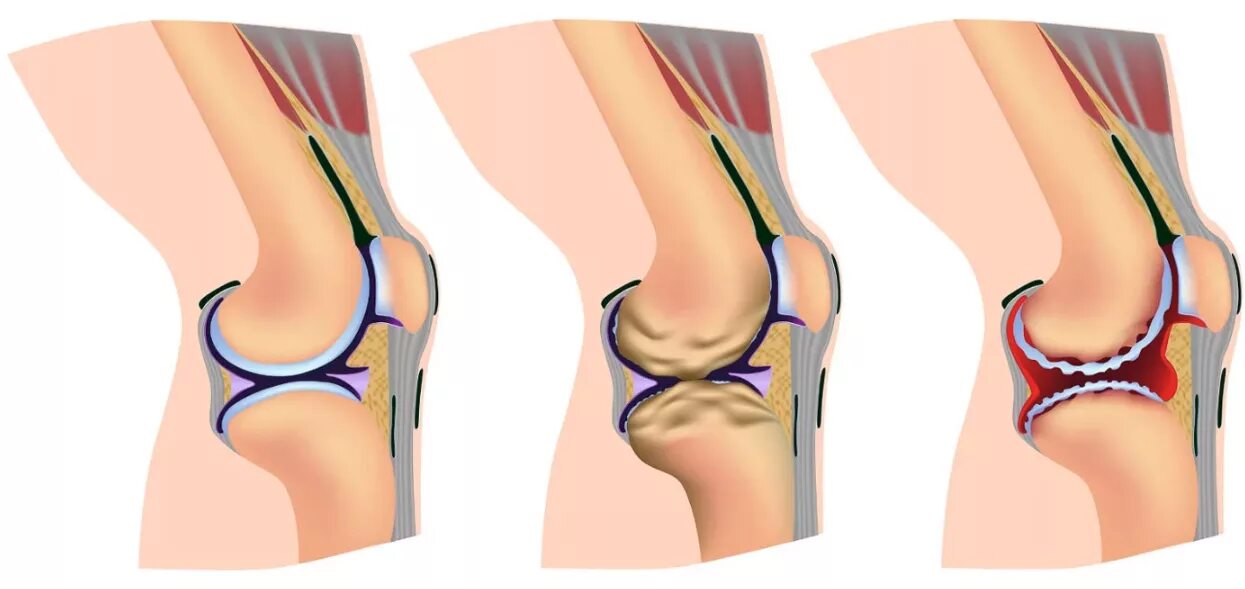

Деформирующий остеоартроз коленного сустава. деформирующий артроз суставов патогенез. разрушение хрящевой ткани коленного сустава. сустав при остеоартрозе.

Деформирующий остеоартроз. деформирующий артроз коленного сустава 1. деформирующий остеоартроз 1 степени коленного.

Деформирующий остеоартроз коленного сустава 1. деформирующий остеоартроз коленного сустава степени. деформирующий остеоартроз 1 стадия. стадии деформирующего остеоартроза коленных суставов.

Классификация остеоартроза коленного сустава. деформирующий остеоартроз механизм развития. артроз 1 степени коленного сустава классификация. деформирующий гонартроз 1 степени коленного сустава.